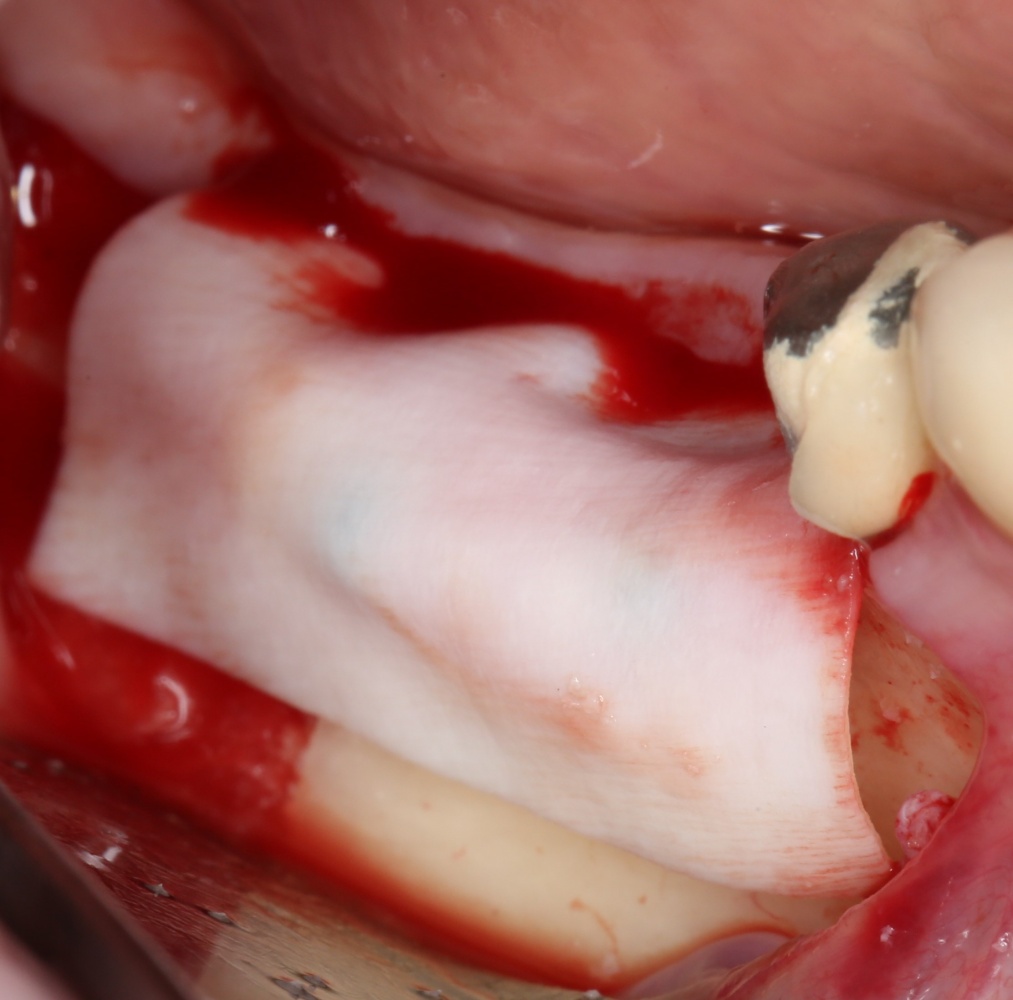

Наложение швов.

Если на этапе разреза и формирования раны всё сделано правильно, то наложение швов не вызывает особых трудностей. Периостотомия или послабляющие разрезы на периосте не требуются (ни практически никогда не требуются). А сами швы получаются аккуратными и герметичными:

Обрати внимание, что все шовные лигатуры находятся в пределах кератинизированной десны. Это позволяет избежать деформации тканей и лишних рубцов. В наиболее уязвимых местах (около зубов) шовные лигатуры лучше продублировать.

Если бы мне пришлось делать это сейчас, то я бы использовал непрерывный «матрацный» шов. Он удобнее, быстрее в наложении и комфортнее для пациента. Минус — если распускается, то распускается весь. К тому же, его очень неудобно снимать.

Несмотря на то, что уже тогда мы широко использовали непрерывные швы в подобных случаях, здесь я, во-первых, зассал (может распуститься), во-вторых, снятие швов предполагалось в поликлинике по месту жительства пациентки, и мне не хотелось, чтобы там при снятии швов начудили. Как выяснится позже — зря беспокоился.

Неизменно одно — в таких операциях мы использовали и до сих пор используем нерезорбируемые монофиламентные шовные материалы, поскольку они наиболее гигиеничные. Чтобы острые концы нитей не беспокоили пациента, их можно оплавить нагретой гладилкой или гуттаперчевым плаггером.